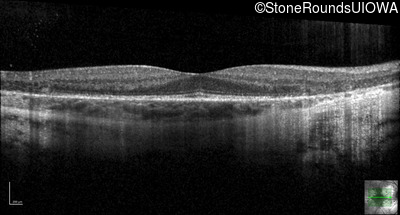

Optical Coherence Tomography - Left - 20/12.5 -2

Exemplar / OCT Stack